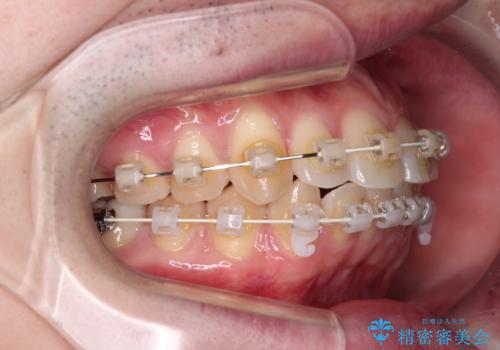

- 上下前歯のデコボコを気にして来院された患者様です。

マウスピース矯正でもワイヤー矯正でも対応可能でしたが、インビザラインによる自己管理が煩わしいとのことで、ワイヤー装置にて矯正治療を行うこととしました。

口元はやや突出感がありましたが抜歯矯正をするほどではないため、舌突出癖を改善するトレーニングをしっかりと行っていただき、現在よりも唇が閉じやすい位置に仕上げていくこととしました。

下顎前歯が思っていた以上に動きが悪く、想定よりも期間がかかってしまいました。

矯正治療後には気になっていた銀歯をセラミックで自然な色に仕上げました。